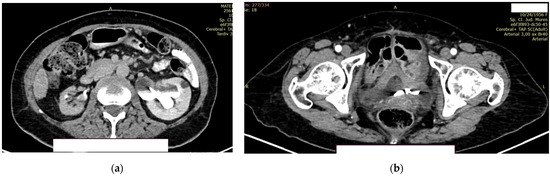

The right kidney is hypotrophic, with the presence of ureteral stent, without stones, and without stasis and presence of secretion. The left kidney showed a normal position of the stent, II/III grade hydronephrosis, secretion, and excretion. A retroperitoneal lymph node, measuring up to 10 mm, was observed, with some calcification (Figure 9a).

Figure 9.

Contrast CT aspect. (a) The right kidney is hypotrophic, with a ureteral stent in place, no stasis, and secretion present. The left kidney also has a ureteral stent, with grade II/III hydronephrosis, and both secretion and excretion are present. (b) The walls of the urinary bladder are concentrically thickened. It is unclear whether the distal intravesical portion of the ureter has any tumor formation.

In the urinary bladder, concentrically thickened walls are described. It cannot be assessed if the distal, intravesical portion of the ureter presents tumors formation (Figure 9b).